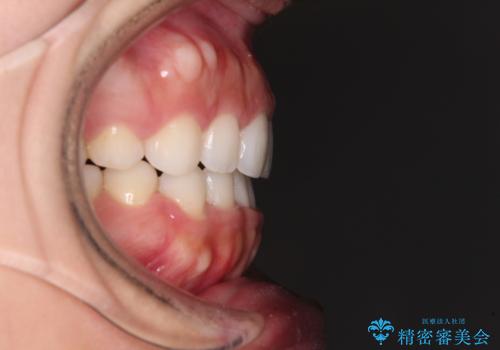

目立たない装置で横顔のシルエットを改善 ハーフリンガルでの抜歯矯正

- 矯正装置

- ハーフリンガル

- 口元の突出感を気にして来院された患者様です。

上下左右の第一小臼歯4本を抜歯して口元を下げる治療計画としました。